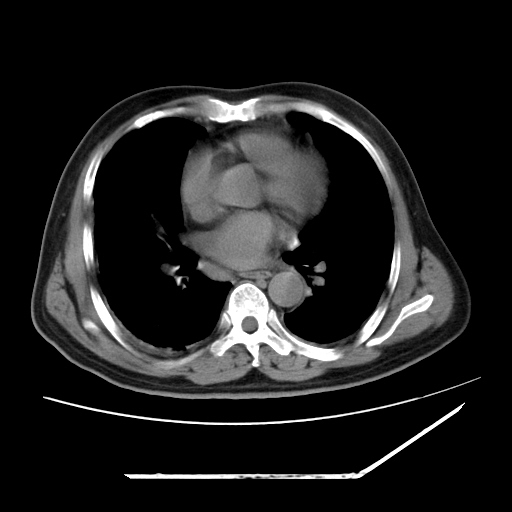

男,57,畏寒,发热

两肺野多发大小不一高密度灶,纵膈内见肿大淋巴结,要考虑转移瘤可能。双侧胸腔少量积液。

1)考虑两肺感染性病变(金黄色葡萄球菌肺炎?);建议抗炎治疗后复查排除其他。2)双侧少量胸腔积液。